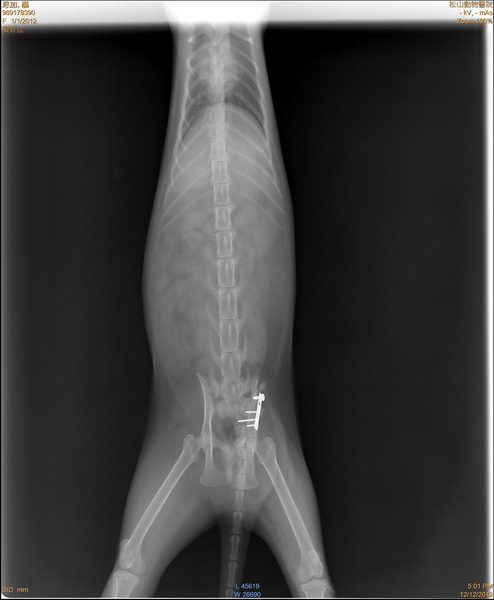

主題: 松江市場車禍骨盆腔骨折的虎斑白 申請者姓名: 蔡葦澄 花色: 申請日期: 2012-12-22 14:46:33 申請者部落格: 申請者臉書網址: 所在縣市/合作醫院: 台北市/恩加動物醫院 治療費用: 6500元 需求人數: 15人 已結案 (2013-08-06 13:46:15) 報名人員: Jill(已付款)、簡絜(已付款)、簡絜(已付款)、莊孝國(已付款)、李安妮(已付款)、Uu、火鳳貍(已付款)、Bella(已付款)、Weili Chang(已付款)、Jess(已付款)、CrystalBall(已付款)、黃先生、zofia(已付款)、Grace Kulai(已付款)、Weiwen Tu(已付款)、蔡郁亭、ming(已付款)、hero178(已付款)、 候補人員: 動物病情說明: 松江市場被車撞的貓咪,骨盆腔骨折被送往收容所,掃晶片發現是市政府TNR的貓咪,由晶片找到負責志工,但已失聯,動保處也沒有相關的訊息,貓咪還需要持續醫療,放任不管直接回置肯定喪命,很謝謝TNR協會的幫忙,讓這隻貓咪得到好的醫療,現在已經康復回置,也請市場的愛心媽媽看顧,醫療住院的費用還請大家幫忙。